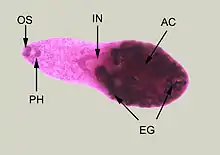

In 1851, during an autopsy, Bilharz discovered an obvious worm from the portal vein connecting the urinary tract of a dead soldier. It was the first time anyone had seen a parasitic worm that lived inside a blood vessel. Not really knowing what kind of worm it was, he wrote to his former zoology professor von Siebold at Breslau on 1 May 1851:[23]

As unique among flukes, the schistosomes have two bodies – a female which is like a roundworm and a male which is curled-up fluke – that are combined permanently (a condition called in copula) to make up individual adult worms.[25] Bilharz had discovered a male fluke. He knew it has similarities to other flukes, especially the two mouth-like suckers (now called oral sucker or acetabulum and ventral sucker), for which he immediately used the name Distomum, a Greek for two mouthed.[26] But the rolled-up body made him think that it was a roundworm. At the end of May, he found a female specimen from another corpse that was all wrapped up by the same kind of worm he had discovered. It occurred to him that the worm was an extraordinary fluke, exclaiming, "Something more wonderful, a trematode with divided sex."[27] All previously known parasitic flukes were hermaphrodites with both male and female reproductive organs in the same individual, a condition called gonochorism.[28] Describing his observation in a letter to von Siebold on 18 August, he wrote:

Bilharz was able to find the male fluke rolled itself up to form a canal in which the female resided, and he named the canal as gynaecophoric canal.[29]

By March 1852, Bilharz also found many eggs from the bladders of the fluke-infected individuals, indicating that those were of the parasites. He could not establish what the eggs did to cause the disease and suspected them as the cause of kidney stone (nephrolithiasis) and other kidney problems. Griesinger had thought that the fluke caused dysentery, but Bilharz found that it was responsible for urinary tract diseases including haematuria as well.[17] He made the first vivid diagrammatic description of the worms and the eggs on 1 December 1881 in a letter to von Siebold. In it he gave the full scientific name Distomum haematobium; the specific name referring to the unique habitat of the fluke in the blood vessels.[27] Von Siebold reported the discovery in Zeitschrift für Wissenschaftliche Zoologie, the journal he edited, in 1852.[30] Bilharz then published in the following volume of the same journal the complete description of the parasite structure and the disease it caused.[31][32] He referred to the disease as "endemic haematuria of warm climates" and the "dysenterische Veränderung des Dickdarms" (dysenteric pathology of the colon).[33] Bilharz then in early 1852 discovered the embryo (now called miracidia; singular, miracidium) developed from the egg in water, and recorded:

Discovery of Schistosoma mansoni

When Bilharz found parasite eggs from infected individuals in March 1852, he noted unique characteristic of schistosome eggs, as each egg has a spine, which he called "pointed appendage."[34] He observed the spiny eggs in the bladder as well as in the intestine. He wrote to von Siebold that some of the eggs were different in having terminal spines while some had lateral spines.[52] Bilharz also noted that the adult flukes were different in anatomy and number eggs they produced.[53] His drawings depicted which were later identified as those of S. mansoni adults.[6]